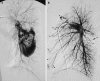

This pictorial review is based on our experience of the follow-up of 120 patients at our multidisciplinary center for hereditary hemorrhagic telangiectasia (HHT). Rendu-Osler-Weber disease or HHT is a multiorgan autosomal dominant disorder with high penetrance, characterized by epistaxis, mucocutaneous telangiectasis, and visceral arteriovenous malformations (AVMs). The research on gene mutations is fundamental and family screening by clinical examination, chest X-ray, research of pulmonary shunting, and abdominal color Doppler sonography is absolutely necessary. The angioarchitecture of pulmonary AVMs can be studied by unenhanced multidetector computed tomography; however, all other explorations of liver, digestive bowels, or brain require administration of contrast media. Magnetic resonance angiography is helpful for central nervous system screening, in particular for the spinal cord, but also for pulmonary, hepatic, and pelvic AVMs. Knowledge of the multiorgan involvement of HHT, mechanism of complications, and radiologic findings is fundamental for the correct management of these patients.